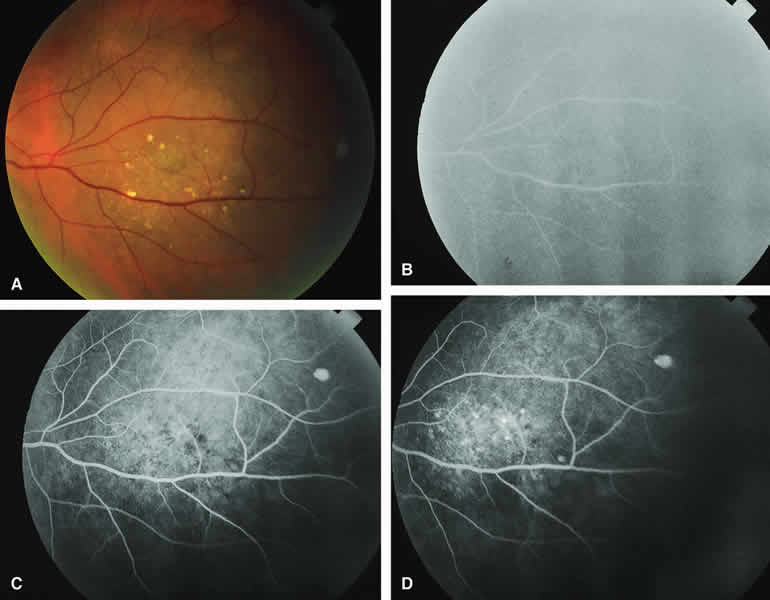

Choroidal Nevus with Drusen and Clumps of RPE Hyperplasia

If a choroidal nevus has drusen and RPE alterations on its surface (see Fig. 4A), fluorescein angiography (Fig. 4B, C, and D) tends to show patchy or stippled window defect hyperfluorescence corresponding to foci of RPE depigmentation, fluorescence blockage by clumps of RPE hyperplasia on the surface of the lesion, and late staining of at least some of the drusen. These features are not usually as evident on ICG angiography as they are on fluorescein angiography.